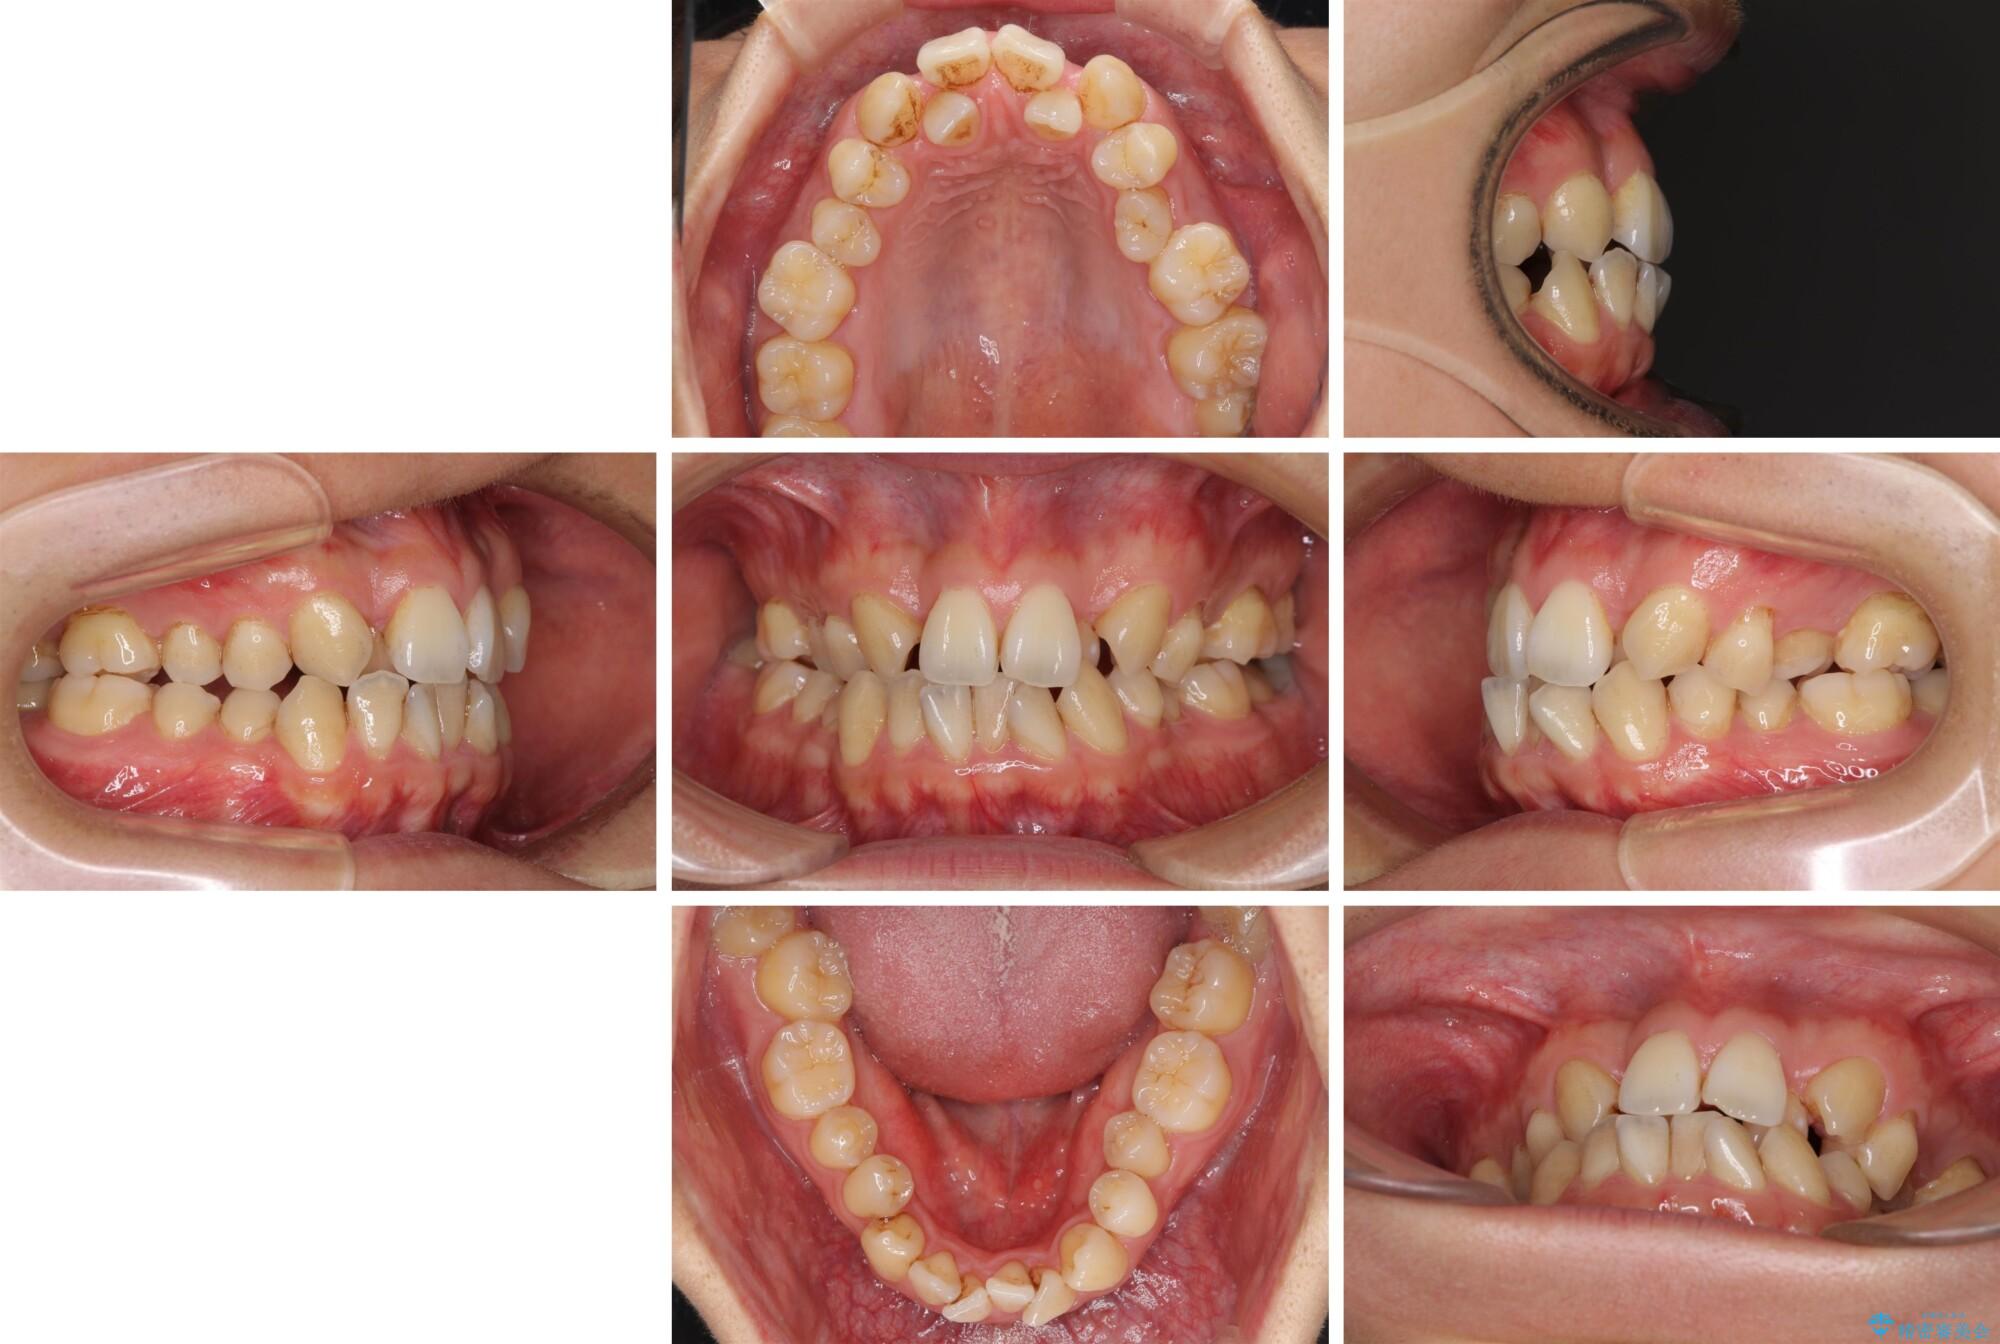

重なり合って磨きにくい前歯 ワイヤー装置での抜歯矯正の症例写真重なり合って磨きにくい前歯 ワイヤー装置での抜歯矯正